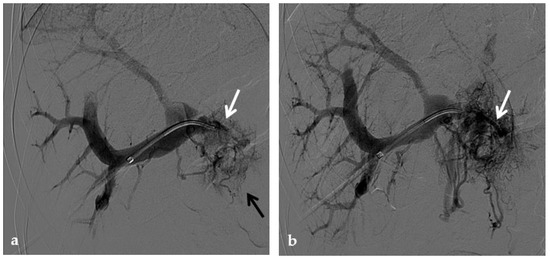

Figure 9.

Anteroposterior view of a percutaneous transhepatic portography imaging series performed for chronic complete portal vein thrombosis with cavernous transformation in an 11-year-old boy with a history of gastrointestinal bleeding and portal hypertension 10 years after deceased-donor orthotopic liver transplantation (split II–III) for biliary atresia. (a) Portography image shows a regular representation of the segment 3 portal branch, while the segment 2 portal branch has a peripheral defect of opacification due to flow reversal, resulting from portal cavernoma and extrahepatic capsular feeding from gastric vessels (black arrow). Complete occlusion of the extrahepatic portal vein at the hepatic hilum (white arrow) is demonstrated. (b) Portography image shows the opacification of a very tiny vascular structure (arrow) which represents what remains of the thrombosed extrahepatic portal trunk. (c) Fluoroscopy image shows angioplasty with a non-compliant 8-mm balloon catheter performed on a stiff guidewire which was advanced across the obstructed tract. (d) Control portography shows a re-expanded extrahepatic portal vein (arrow) with normal spleno-portal opacification. Portal vein thrombosis recurred one year after treatment and required repeated angioplasty and metal stenting (shown in the next figure).

No consensus exists regarding the optimal indication for stent placement in PVT. Portal vein stent placement seems to be a safe and effective method for the treatment of post-transplantation PVT in pediatric recipients. The intermediate-term portal vein patency after stent placement is excellent [70] (Figure 10). In one study, after recanalization of the segment of portal vein affected by thrombosis through PTA, if an elastic recoil of more than 50% of the normal extrahepatic portal vein, a residual pressure gradient of more than 5 mmHg or a vascular dissection were found, stent placement was performed [8]. Several other investigators have reported a 100% portal vein patency rate after stent placement with various follow-up times [71,72]. These patency rates are superior to those previously reported with balloon angioplasty alone (27–50%) [73].

Figure 10.

Anteroposterior view of a percutaneous transhepatic portography imaging series in the same patient as in Figure 9. (a) Portography image shows recurrence of complete extrahepatic portal vein thrombosis (white arrow) 1 year after the first angioplasty treatment. Flow reversal in the segment 2 portal branch resulting from portal cavernoma is still evident (black arrow). (b) After transhepatic portal vein recanalization with the angiographic catheter, the splenic portogram shows jejunal cavernoma (white arrows) and gastric (black arrow) varices, due to complete obstruction of the extrahepatic portal trunk. Embolization of varices was performed using a mixture of N-butyl cyanoacrylate and iodized oil and metallic coils. (c) Portography image after angioplasty of the extrahepatic portal vein shows successful endoluminal filling of the portal vein, with a restored but still irregular profile (white arrow). Note subtraction artifacts (black arrows) representing lipiodol and coils in the cavernoma and varices. (d) Final portogram performed after deployment of a 10-mm self-expandable bare metal stent to treat residual stenosis of the extrahepatic portal vein; the main portal vein is now regularly opacified with adequate size and both intrahepatic portal branches present hepatopetal flow.